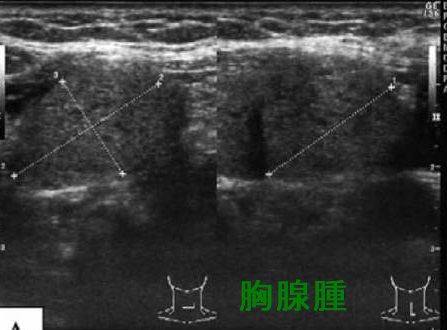

甲状腺超音波(エコー)上、胸腺腫は甲状腺の下に見え、内部不均一な腫瘤で、特徴的な所見に欠きます。小児の胸腺とは異なる見え方です。

心臓の上に乗っかるような形態なので、左に多く、CTで見ると、あたかも甲状腺結節・甲状腺腫瘤・甲状腺腫瘍のように見えます。